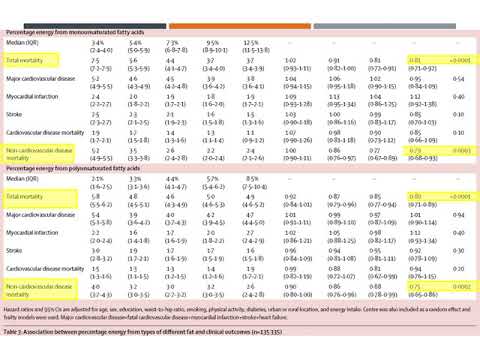

Estudio PURE. Residencia de Cardiología. Hospital C. Argerich. Buenos Aires